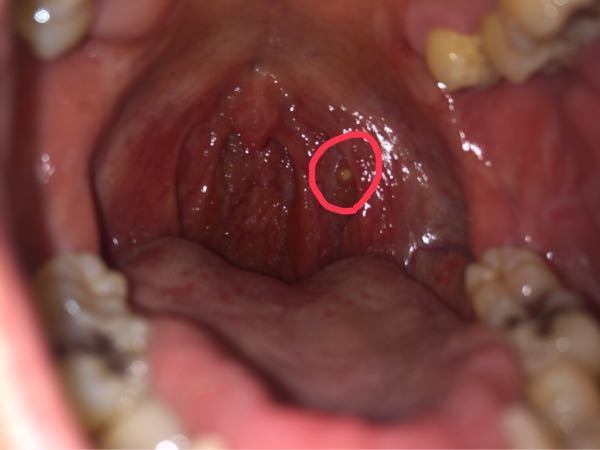

吐き出すときに不快で強い臭いを感じ、その外観は通常よりも厚く、黄色と緑色の間で色が異なり、有名な膿も化膿性物質で構成されています。

この分泌物は炎症過程の結果として生成されます。つまり、喉の膿は、最もよく知られている感染症である扁桃炎や咽頭炎に伴う症状です。

レンサ球菌性咽頭炎

咽頭の細菌感染症であり、高熱、悪寒、嘔吐、喉の痛み、頭痛、腹痛を引き起こします。扁桃腺も充血して肥大し、膿がたまります。

この状態は感染が広がり、中耳炎、髄膜炎、心内膜炎、肺炎などを引き起こしたり、リウマチ熱や糸球体腎炎、つまり腎臓領域の炎症を引き起こす可能性があるため注意が必要です。